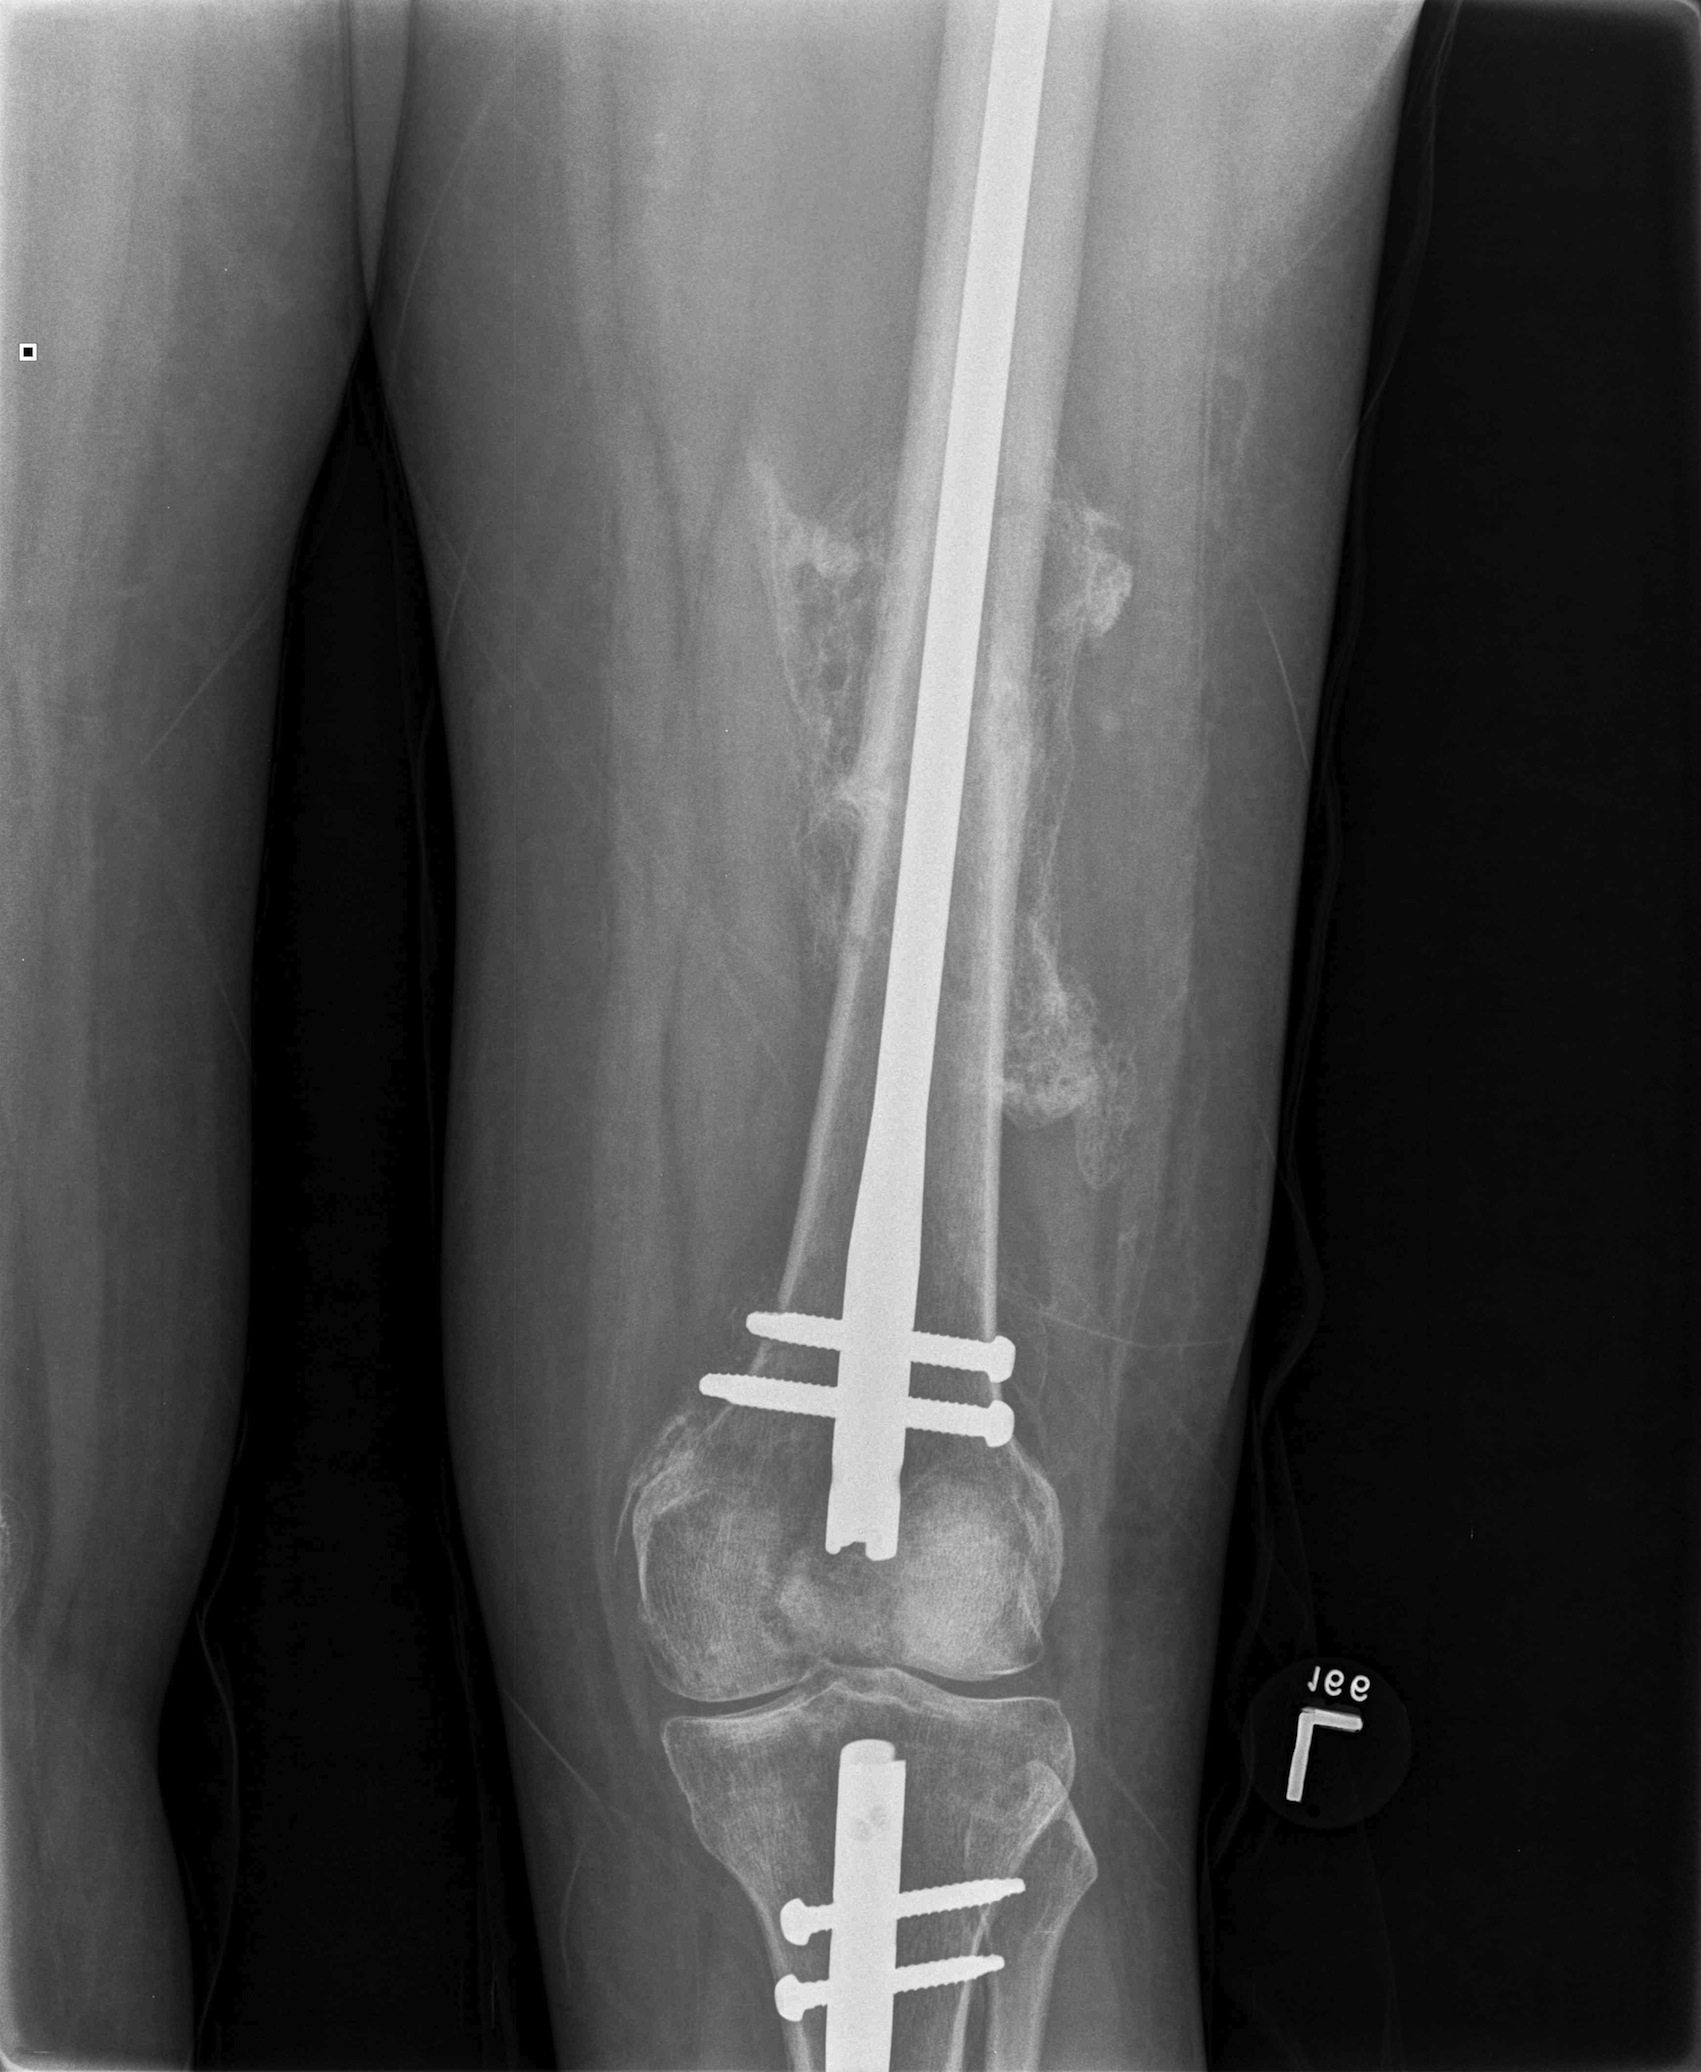

Femoral Shaft Fractures The Bone School

Floating knee A modified Fraser's classification and the results of a Floating Bone On Knee A loose body is essentially a fragment of cartilage or bone that has broken away from the surface of the knee joint. If you feel something strange in your knee joint — like something's floating in there — it may be articular cartilage. Floating knee refers to the knee joint and not necessarily the connection to either long bone. When. Floating Bone On Knee.

From www.injuryjournal.com

Femoral Shaft Fractures The Bone School Floating Bone On Knee When these fragments get trapped between the articular. Floating knee refers to the knee joint and not necessarily the connection to either long bone. If you feel something strange in your knee joint — like something's floating in there — it may be articular cartilage. A loose body is essentially a fragment of cartilage or bone that has broken away. Floating Bone On Knee.

Floating Knee Floating Bone On Knee Floating knee refers to the knee joint and not necessarily the connection to either long bone. Loose bodies in the knee joint are small fragments of cartilage or bone that move freely around the knee in joint fluid, or synovium. Although tibial and femur fractures are not uncommon, having injuries to both bones simultaneously on. Bone and cartilage fragments in. Floating Bone On Knee.